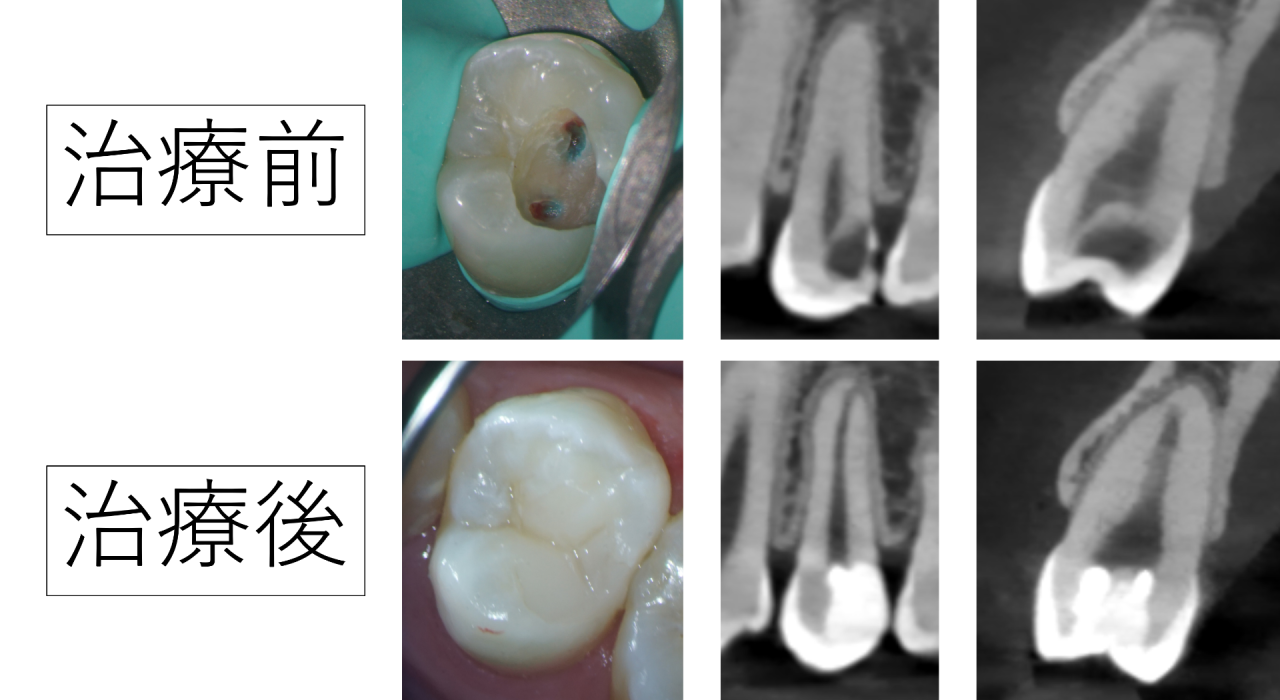

VPT(Vital Pulp Therapy バイタルパルプセラピー)は、虫歯が深く神経の近くまで進行している場合や、神経が一部炎症を起こし感染している場合でも、条件が整えば神経を保存する治療です。

間接覆髄は、虫歯が神経のすぐ近くまで進んでいる場合に、神経を露出させずに保護する治療です。

深い虫歯を取り除くと、神経まであとわずかという状態になることがあります。その際、神経を傷つけないよう慎重に虫歯を取り除き、神経の近くに保護材を置いて封鎖します。

直接覆髄は、虫歯を取っていて神経が小さく出てしまった(露出した)場合に、神経を保護して残すことを目指す治療です。

虫歯が非常に深いと、治療中に神経が露出することがあります。そのとき、神経の炎症や出血の状態などを診査し神経が残せると判断すれば、露出した部分をきれいに消毒し、必要な処置を行った上で、神経を守る材料を置き、細菌が入らないようにしっかり封鎖します。

特に重要なのが「出血の状態」です。

虫歯を取り除いた後、神経から出血します。その出血が数分以内に落ち着くかどうかは、神経の炎症がどの程度かを示す重要な目安になります。

長時間止血できない場合は、炎症が広範囲に及んでいる可能性が高く、神経の保存は難しいと判断することがあります。